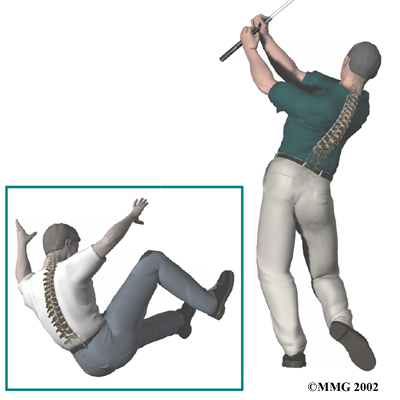

Less commonly, a thoracic disc may herniate suddenly (an acute injury). A thoracic disc may herniate during a car accident or a fall. A thoracic disc may also herniate as a result of a sudden and forceful .

Less commonly, a thoracic disc may herniate suddenly (an acute injury). A thoracic disc may herniate during a car accident or a fall. A thoracic disc may also herniate as a result of a sudden and forceful .

Less commonly, a thoracic disc may herniate suddenly (an acute injury). A thoracic disc may herniate during a car accident or a fall. A thoracic disc may also herniate as a result of a sudden and forceful

Less commonly, a thoracic disc may herniate suddenly (an acute injury). A thoracic disc may herniate during a car accident or a fall. A thoracic disc may also herniate as a result of a sudden and forceful